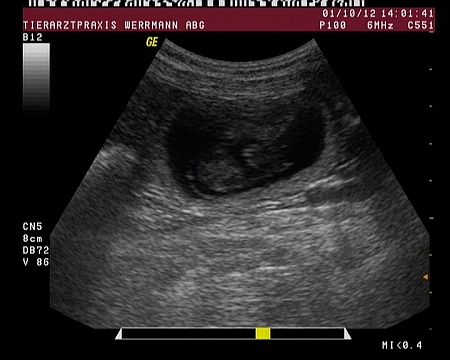

Hier sehen sie zwei Fruchtblasen mit den darin liegenden Welpen.